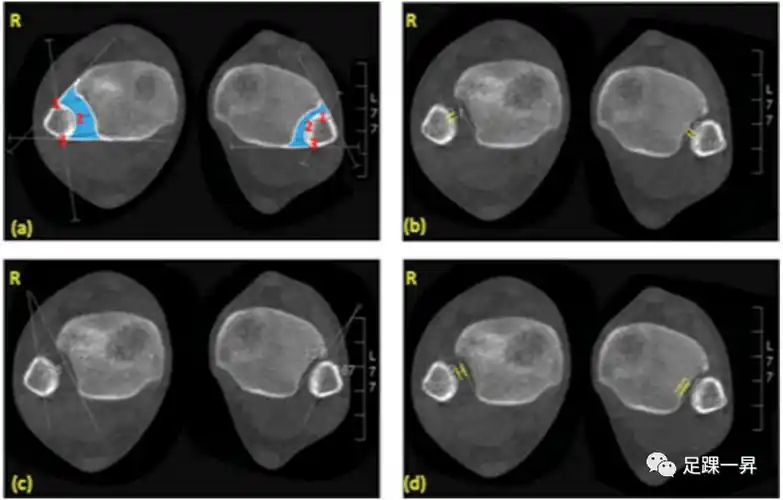

表3为下胫腓联合损伤的ct测量方法.

横断位软组织窗ct冠状位软组织窗,骨窗x线正侧位外院mri提示右小腿背